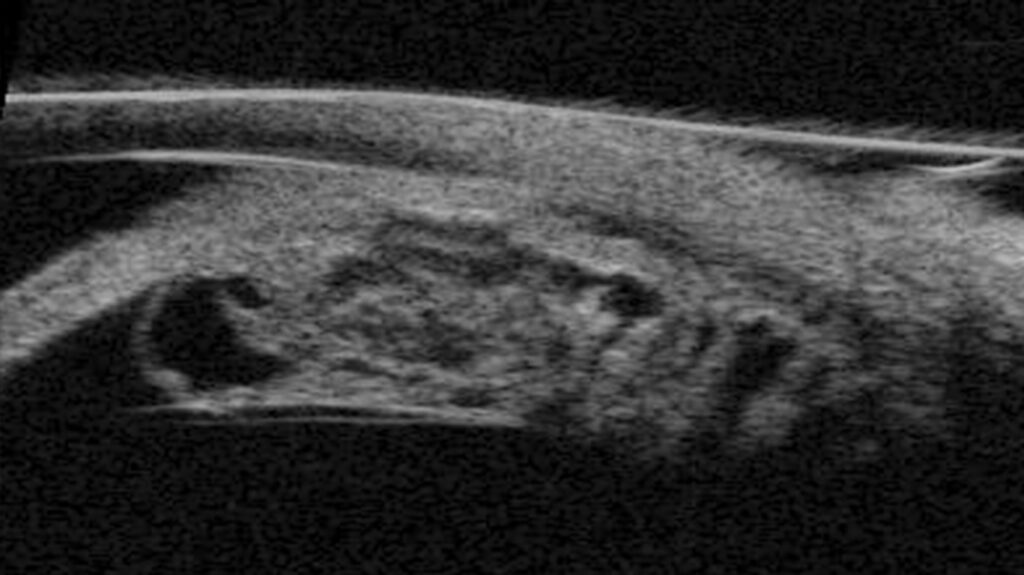

Update Jady (6)

Veröffentlicht am 7. September 2022Volle Größe 1366 × 767